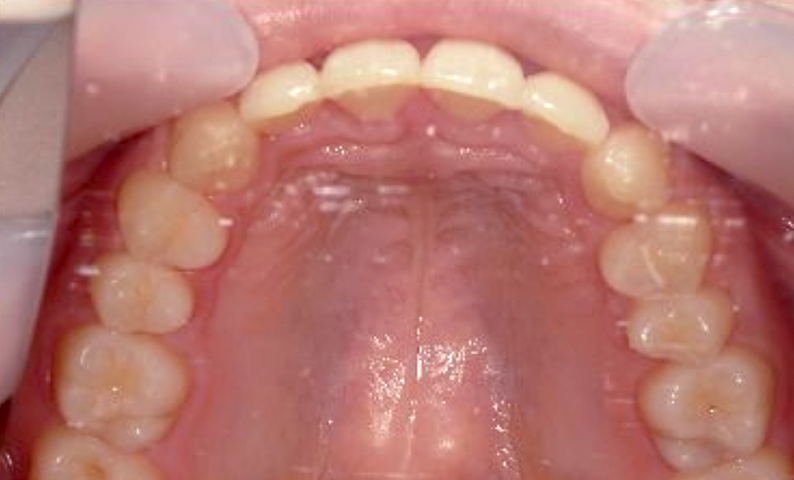

症例_021 上顎だけの部分矯正

治療期間:8ヶ月金額:30万円+税女性前歯のガタガタ八重歯上の前歯だけ

| Before | After |